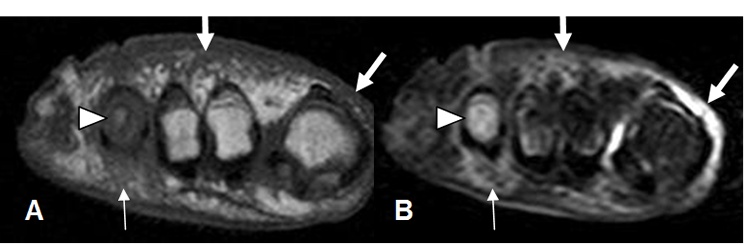

Fig 125 C. Pie diabético.

A: RM axial en T1 simple, B: RM axial en STIR y C: RM axial en T1 con contraste.

Pie diabético con cambios inflamatorios en los músculos plantares, hipointensos en T1 e hiperintensos en STIR. (Flechas delgadas). Con el contraste hay zona que no realza, sobre el 5º metatarsiano, por la presencia de tejido desvitalizado. (Flecha gruesa).